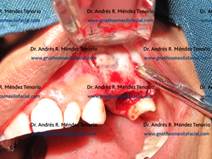

CIRUGIA PREIMPLANTES

![]() |

| Paciente con resto radicular y defecto óseo después de su extracción | |

| Regeneración ósea con injerto de hueso y PRP y resultado de la cicatrización después de 3 meses | |

| Transcurrido ese tiempo, se realiza la inserción del implante óseointegrado | |

| Implante colocado y sutura de herida | |

| Una vez que el implante se integró, se termina la rehabilitación con una corona | |

|

Radiografía antes y después del proceso regenerativo (falta rx inicial) |